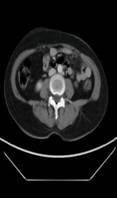

术前MRI检查